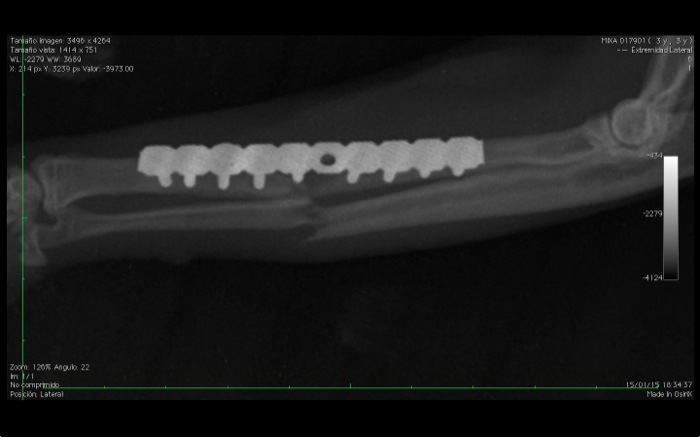

Ha durado mas de lo aconsejable la cirugía, 2h y 45 min. pero el resultado es estable con 2 corticales firmes por tornillo. La evolución a partir de aquí va a depender de un manejo estricto del entorno del paciente felino.

El resultado es satisfactorio en esta proyección y aunque el cúbito no se alinea perfectamente el apoyo con este miembro derecho es óptimo al mes.

El codo queda radiológicamente bien. Al mes utiliza ambos miembros aunque en este la recuperación aún no es completa. Es necesario esperar y dar tiempo para ver si alcanzamos la misma función que en el otro miembro con total movilidad. Aunque a nivel óseo podemos tener un buen pronóstico a medio plazo el daño articular fue muy amplio y habrá que dar tiempo para valorar la retirada en pocos meses de los implantes. A largo plazo y ante lesiones de esta envergadura siempre tenemos el riesgo de la aparición de artrosis